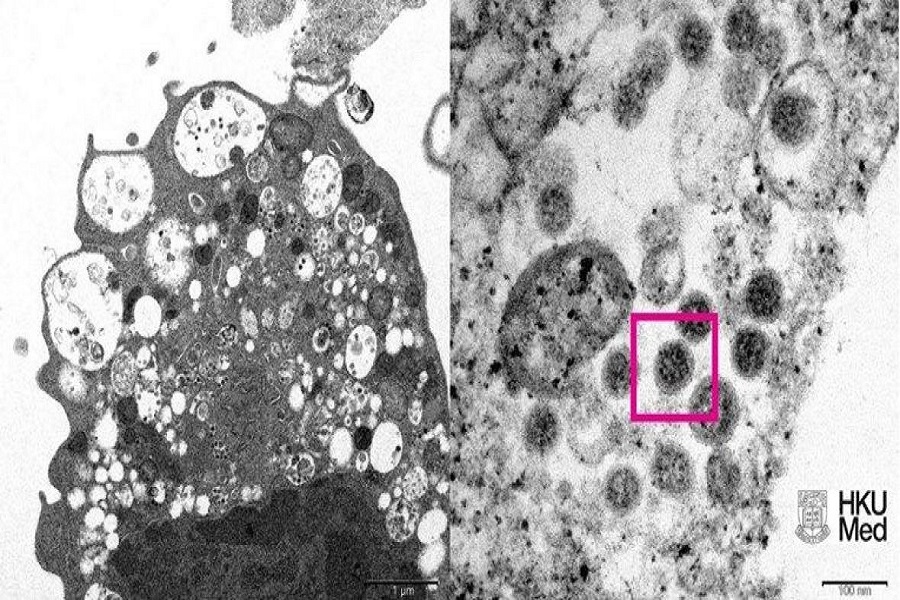

Universiteti i Hong Kongut publikoi sot fotografinë e parë mikroskopike të omicron, një variant i ri i koronavirusit. Një fotografi e omicronit është marrë me një mikroskop elektronik.

Pjesa e majtë e fotos tregon një mikrografë elektronike të një qelize veshkash majmuni pas infeksionit me omikron. Fotoja tregon dëmtimin e qelizave dhe grimcat e vogla të zeza të virusit.

Pjesa e djathtë e fotografisë është një version i zmadhuar i pjesës së majtë dhe tregon të njëjtën qelizë të infektuar. Në atë pjesë të fotos, mund të shihni një sërë grimcash virale me thumba karakteristike për koronaviruset.